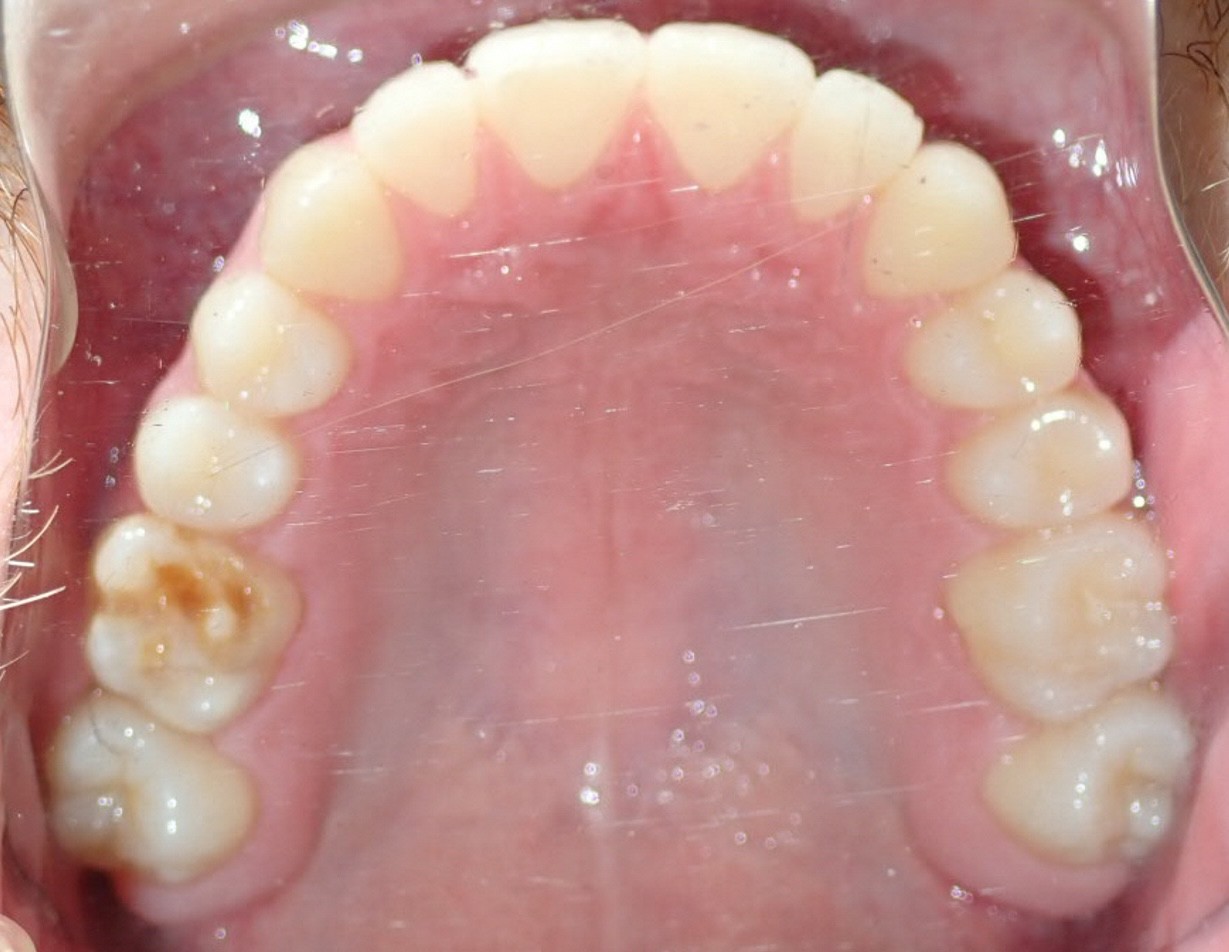

Initial treatment

INTRAORAL